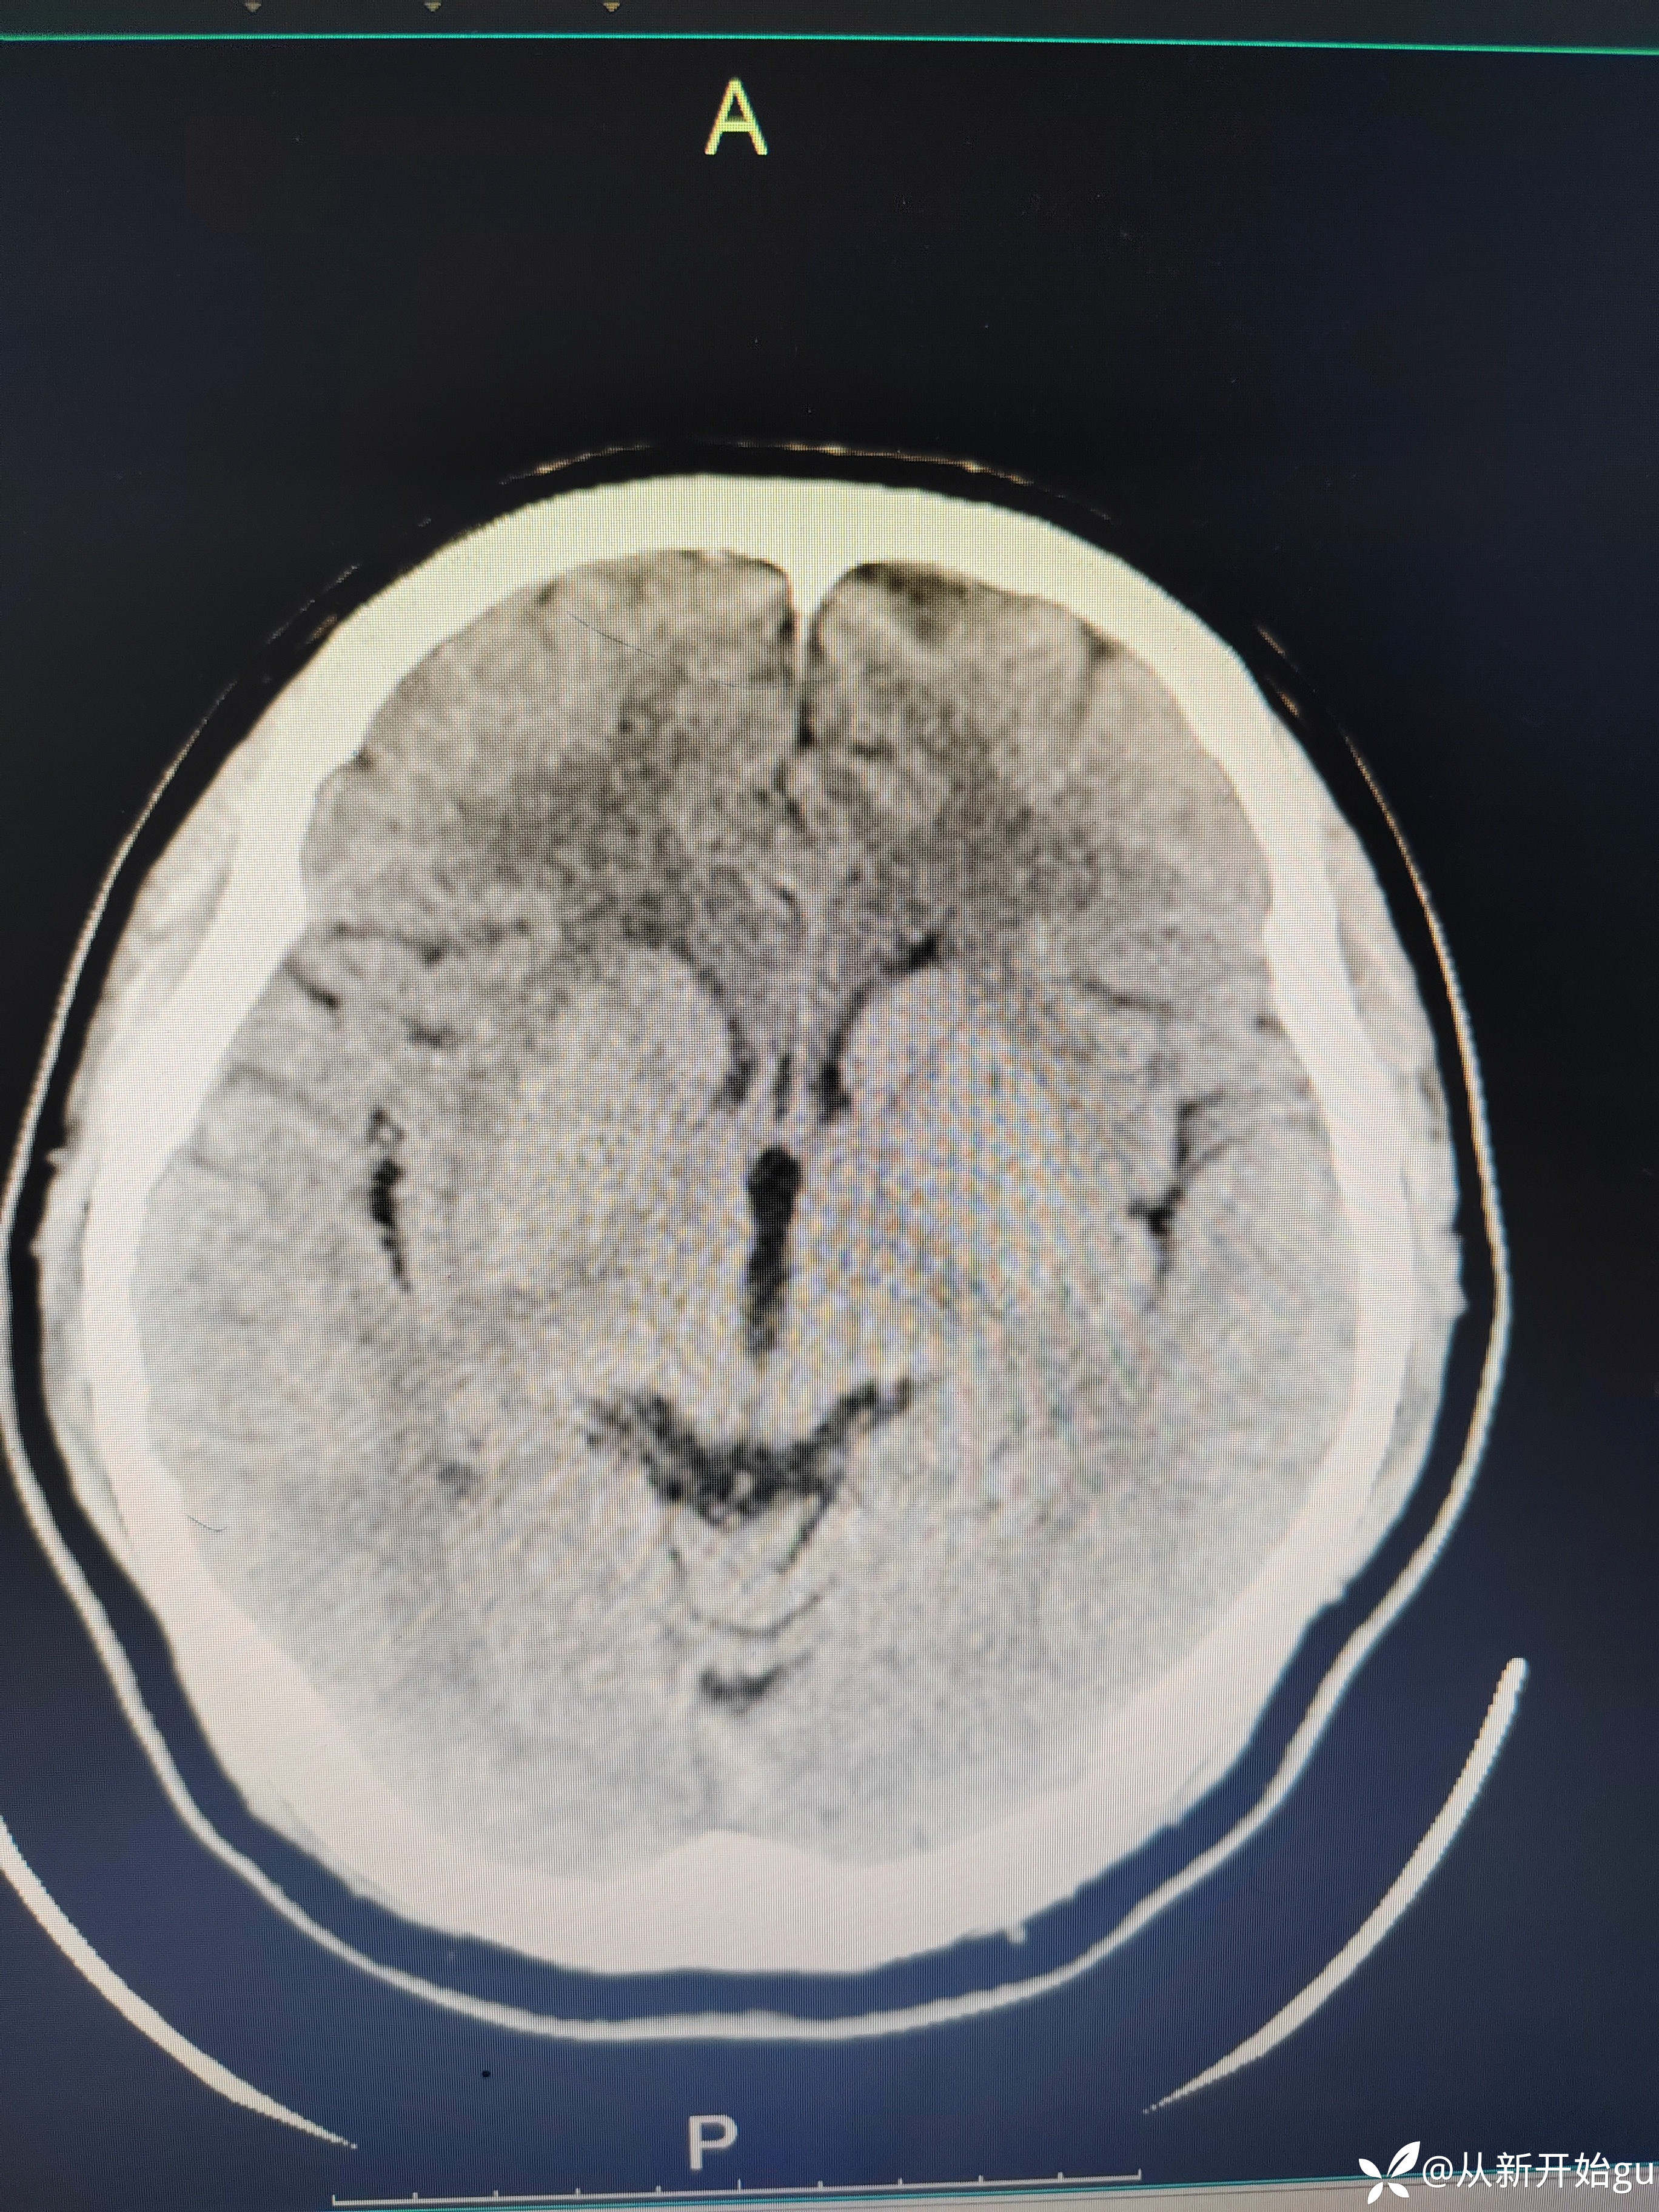

患者左下肢屈膝位—伸直过程中,左下肢费力感,左下肢僵硬感。常规我是会做个DWi明确一下,晚上都11点了(心疼放射科兄弟,就没做),直接和家属谈了一句溶栓,简要的说明,可溶可不溶,考虑病灶比较小(致残不致残都承担着同样的风险,个人不太想给溶)。家属比较积极,最后给予溶栓治疗。溶栓后无明显改善,第二天晨起诉明显减轻,但较正常下肢还是有区别。完善核磁检查(发病10小时做的)无新发梗死灶。血管如图所示:

患者目前肌力完全恢复,如果不溶的话,也许会有后遗症?无从考证。